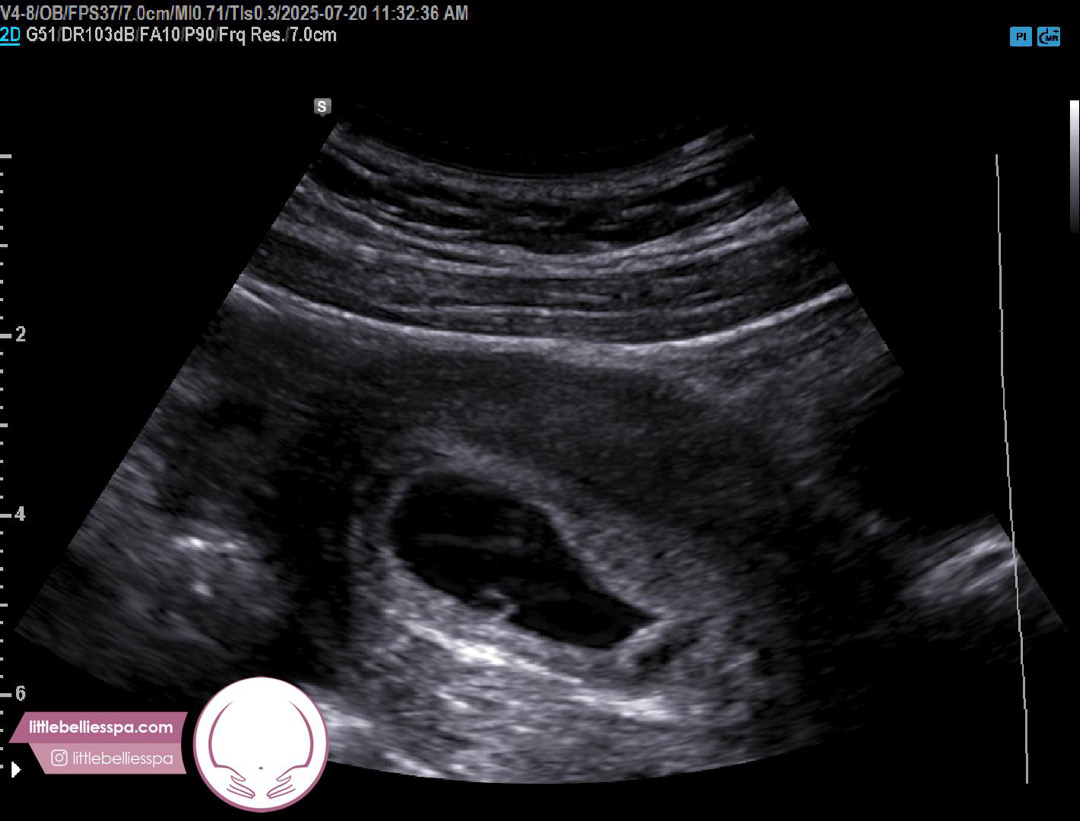

6주0일 복부초음파 보고왔어요(미국)

미국 사는 예비맘이에요~여기서는 바로 병원갈수기없기때문에 8주에 의사쌤보러가기전에 사설업체 가서 초음파 보고왔어요. (사설업체는 의사가 아니라 초음파 테크니션이 봐줘요) 아무래도 병원은 아니라 그런지 복부초음파로 해주시더라구요. 애기집,난황,애기 콩닥콩닥하는거까지 보고왔는데 심장소리는 못들었어요ㅠㅠ 복부초음파라그런지 화질이 좀 떨어지는거같아서 다른분들처럼 난황이 다이아처럼 이쁘게 딱! 안보이는데 괜찮은건지 봐주세여~~ 그리고 그 테크니션이 지나가는말로 애기집이 똥~그랗지않아서 그게조금걱정이지만 나중에 너의사보러가면 더 자세히 설명해줄거야~하고말았는데 그말이 너뮤걸려요ㅠㅠ 찾아보니 초음파 각도에따라 구럴수있다고 걱정하지말라는데 맞나요? 초음파보고와도 걱정투성이네요ㅠㅠ😭😭 아! 또 애기크기가 0.42cm로 나왔는데 괜찮은 크기인가요?